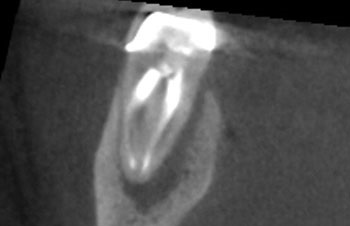

Case 9: A crack ‘seen’ on CBCT

This patient requested a second opinion after an endodontist advised them to extract tooth #14. The extraction was recommended because the endodontist believed that a VRF was visible on the palatal root on the CBCT. The previous NSRCT and metal post might have given more supportive context for the argument, but the crack “seen” on the CBCT was used to make the diagnosis of VRF.

When radiopaque dental materials, such as obturations or posts, are present in the same plane as the root, CBCT is not effective in identifying VRF. Reconstruction artifacts often present as dark lines that can be misinterpreted as cracks. Furthermore, posts generally look larger than they really are on the CBCT and often appear to perforate root surfaces when they are not. This tooth was not cracked. The periradicular tissues healed completely following nonsurgical re-treatment.

Fig. 34: Preop CBCT COR.